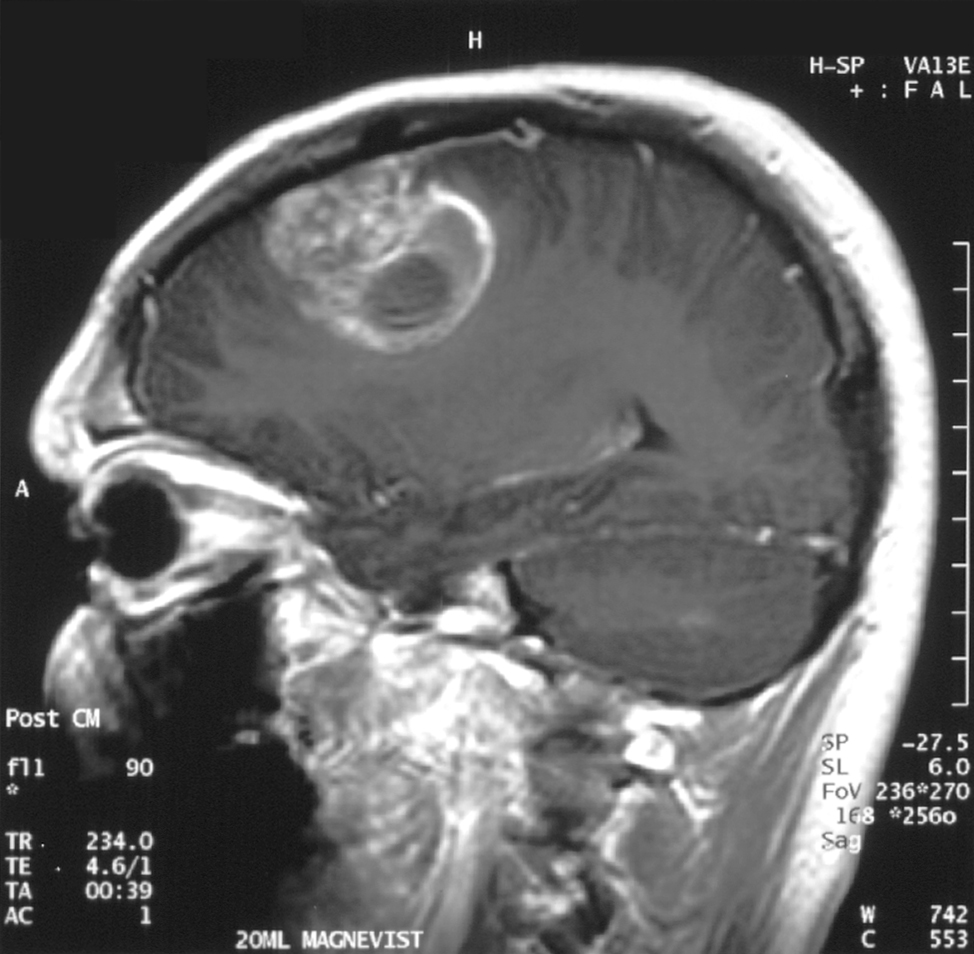

Pentru studiu, cercetătorii au analizat ţesut cerebral uman şi probe de glioblastom tumoral cerebral, o boală incurabilă cu o rată de mortalitate foarte mare.

Oamenii de ştiinţă au utilizat această tehnică şi cu ajutorul său au reuşit să identifice 10 noi transcrieri ale celulelor endoteliale specifice glioblastomului, care nu se găsesc în vasculatura ţesutului cerebral normal.

Aceşti markeri oferă noi informaţii despre biologia glioblastomului şi reprezintă ţinte potenţiale pentru terapia specifică tumorii cerebale.